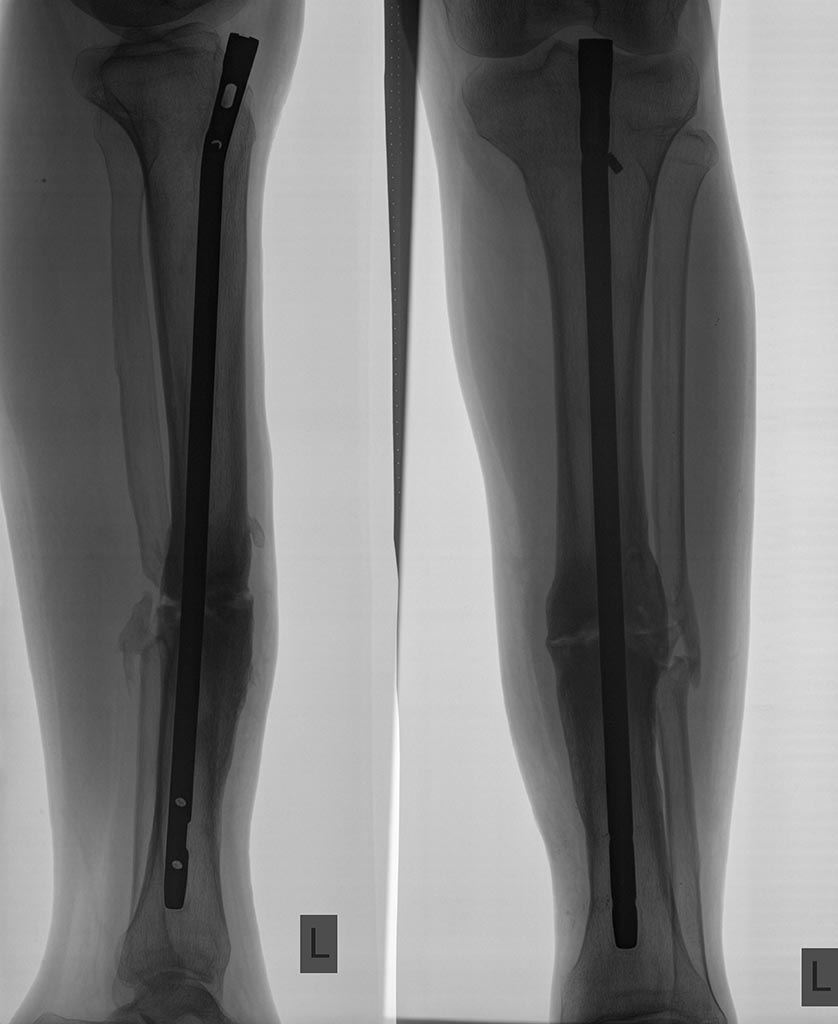

Пациент,19лет,травма в ДТП 1,5года назад ( ЧМТ,перелом бедра,перелом

обеих костей

голени).

Проведен БИОС бедра и голени. Бедро срослось, стержень удален через год.

Вопрос по голени: есть ли шанс на сращение, принимая во внимание возраст

пациента(если ждать,то сколько) или делать реостеосинтез с

рассверливанием сейчас? Клинически пациента ничего не беспокоит.